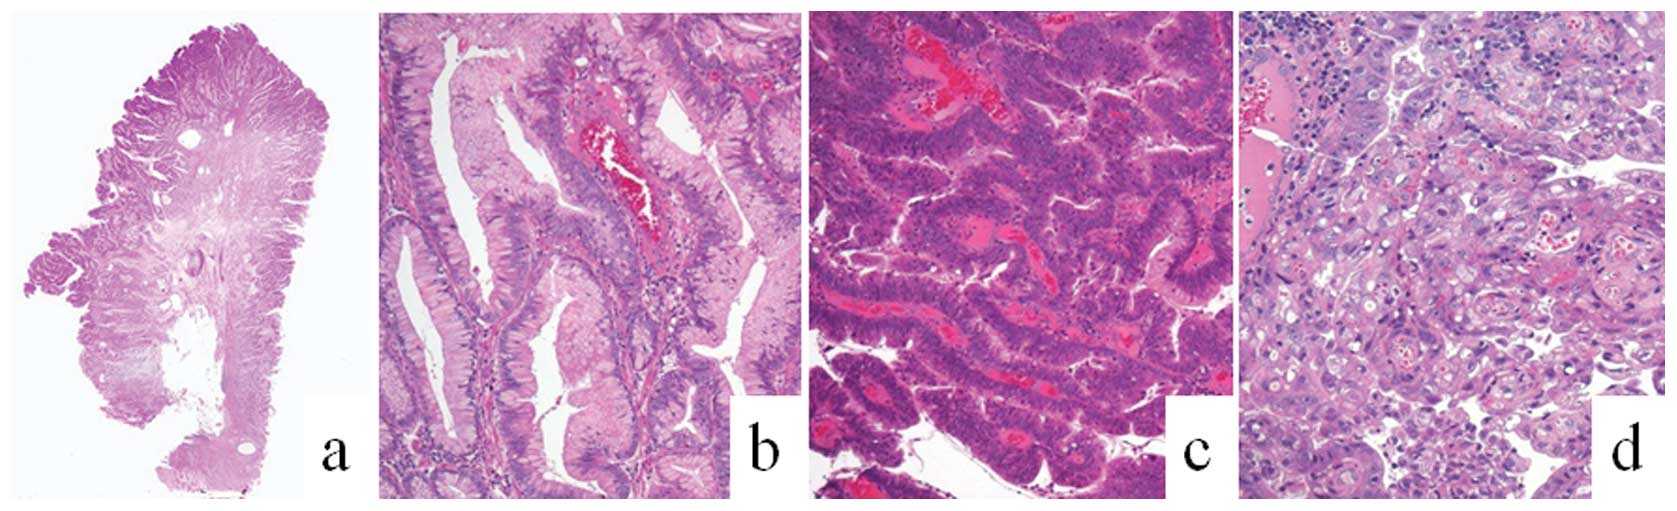

The resected polyps ranged in size between 10 and 40

mm in longitudinal diameter (mean size, 26 mm). All polyps were

regionally composed of intermingled components of plural lesions in

varied proportions. The lesions were basically composed of

hyperplastic foveolar epithelium and intramucosal neoplasia, the

latter of which was categorized as dysplasia and adenocarcinoma.

The carcinomatous components were mainly differentiated as tubular

adenocarcinoma. Although the border between each component was

distinct, the transitional zone was relatively undefined (Fig. 2).